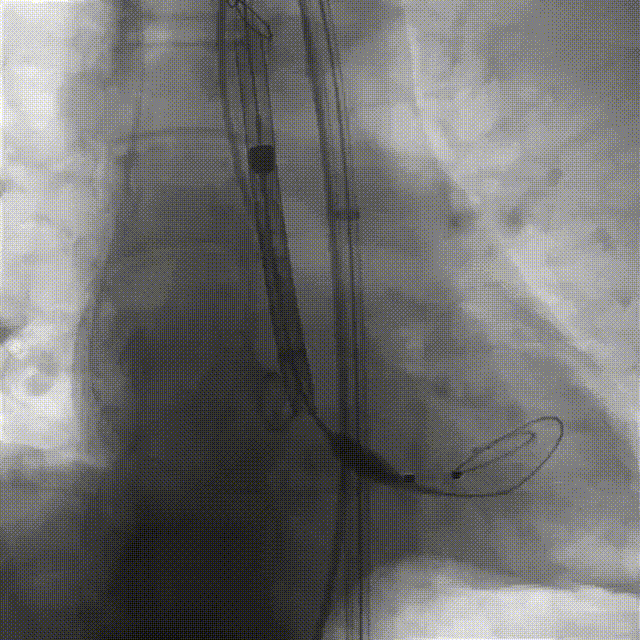

袁祖贻院长 西安交通大学第一附属医院 创新见证中国领跑,数据积累筑牢临床效果 韩克教授 西安交通大学第一附属医院 干瓣技术革新赋能特殊人群治疗,“量体裁衣”筑牢安全防线 患者病史 主诉与现病史:5年前因"血友病,血尿”就诊于当地医院,住院期间行心动超声提示主动脉瓣及二叶瓣畸形,无胸闷气短,无胸痛,咳嗽咳痰,无头晕,恶心呕吐等不适。未予以干预,后规律复查心超,3周前复查心超提示:主动脉瓣二瓣化畸形并重度狭窄,升主动脉内径明显增宽。 既往史:确诊血友病A型40年 术前超声提示:先天性主动脉瓣二叶式畸形,主动脉瓣中度狭窄,升主动脉增宽,左室舒张功能减低,EF73% 术前CT:Type0型二叶瓣,瓣叶增厚无钙化,主动脉瓣环径24.1mm,LVOT23.9mm;双侧冠脉开口高度可,窦部空间可,STJ、升主动脉内径可;预估冠脉低风险;主动脉水平夹角37.1°,主动脉弓角、弓距可;左室内径可;外周入路无明显迂曲,无钙化;双侧股动脉内径可,右侧股动脉低分叉。 手术策略 推荐右侧股动脉为主入路,左侧股动脉为辅入路。右股分叉上方1mm穿刺;仅舒张期时相,需根据球扩结果评估瓣膜尺寸,推荐使用18mm球囊进行预扩;预装AV26瓣膜。 手术过程 在右股动脉穿刺建立通路后,顺利送入大鞘。18mm球囊预扩后评估无腰无漏,后将Prostyle A® AV26瓣膜精准释放于目标位置,术后即刻造影显示无明显反流,无瓣周漏,平均跨瓣压差由术前的100mmHg降至2mmHg,患者血流动力学显著改善,术后超声证实瓣膜启闭良好。 主动脉根部造影 18球囊预扩 定位 稳定释放后脱钩 最终造影形态位置良好 外周血管造影,无血管并发症 术后超声显示无生物瓣位置固定瓣膜功能正常,无瓣周漏。 Prostyle A®预装干瓣——助力临床最优化解决方案 流入端桶状设计:流入端桶状的设计,锚定迅速,有效减少释放步骤,提升植入稳定性; 平衡的收腰设计:二叶瓣患者对瓣膜径向支撑力提出更高要求,Prostyle A®均衡的收腰设计可更好适应二叶瓣解剖,保证了EOA,有效降低了循环崩溃风险,提高瓣膜的耐久性; 预装干瓣 便捷顺安:金仕生物专利抗钙化技术运用纳米技术去除组织内的细胞碎片和磷脂,封闭游离醛基,从根本上阻断了瓣膜钙化的多项因素,显著提升了瓣膜的耐久性;同时,相比较传统戊二醛保存方式,干式存储最大限度的保留心包的亲水亲油平衡,还原组织天然曲柔性,进一步保障了瓣叶开合,保证长期耐久性。 专家简介 袁祖贻 西安交通大学第一附属医院(点击查看专家详细简历) 韩克 西安交通大学第一附属医院(点击查看专家详细简历) · END ·